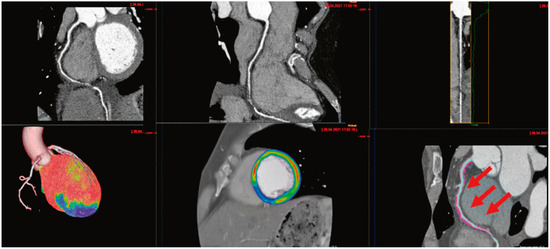

Notre deuxième cas est celui d’une femme de 50 ans avec des antécédents de SCAD de l’artère interventriculaire postérieure 6 ans auparavant. Elle vient aux urgences pour une douleur thoracique oppressive avec irradiation dans l’épaule gauche et la mâchoire, qui a commencé spontanément au repos et a duré 30 minutes. Elle rapporte des symptômes vagaux précédant les douleurs thoraciques (diaphorèse, pâleur, nausées et vomissements). L’ECG d’entrée est sans signes d’ischémie. Le bilan paraclinique est complété par la mise en évidence d’une légère élévation des troponines à 20 ng/l (norme 4–16 ng/l). Au vu d’une possible récidive de SCAD on effectue un angio-CT coronaire qui met en évidence une dissection étendue de l’artère coronaire droite s’étendant de son ostium jusqu’à sa bifurcation entre l’artère interventriculaire postérieure (IVP) et l’artère rétroventriculaire postérieure (RVP) (Figure 2) Cette dissection s’étend dans l’ostium de l’IVP avec à cet endroit une sténose significative subocclusive (99%). L’échographie cardiaque a mis en évidence une FEVG dans la norme malgré une akinésie inféro-septale moyenne et distale. Nous décidons d’administrer un traitement conservateur avec aspirine 100 mg 1×/j. Pendant le séjour, la patiente se plainte également de céphalées et cervicalgies après une manipulation cervicale par un physiothérapeute quelques jours auparavant. Une IRM cérébrale est réalisée et met en évidence une dissection du segment V2 de l’artère vertébrale droite avec une perméabilité résiduelle de l’artère en distalité et sans signe d’AVC associé. Cette patiente présente ainsi un deuxième épisode de SCAD sans facteur de stress précipitant retrouvé et associé avec une dissection de l’artère vertébrale probablement après une manipulation cervicale. Cette présentation rare est évocatrice d’une vasculopathie sous-jacente et le diagnostic d’une dysplasie fibromusculaire est confirmé par la suite.

Figure 2.

Une dissection étendue de l’artère coronaire droite s’étendant de son ostium jusqu’à sa bifurcation entre l’IVP et la RVP avec la region ischémique des segments inféro-septaux moyens et distaux.